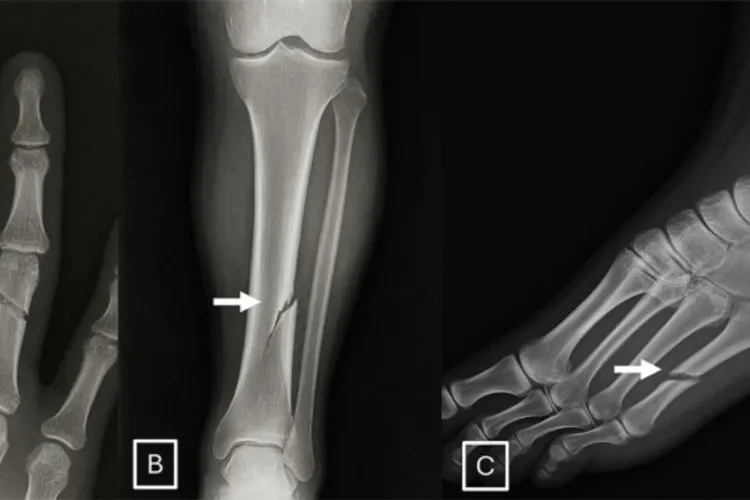

Un studiu recent atrage atenția asupra unui risc major din domeniul medical: imagini radiologice false, generate de inteligența artificială, pot păcăli inclusiv radiologi experimentați. Cercetarea, citată de revista Nature, evidențiază vulnerabilitățile serioase pe care această tehnologie le introduce în sistemele de diagnostic. Studiu internațional: cât de ușor pot fi confundate imaginile În cadrul cercetării, 17 radiologi din 12 spitale, situate în șase țări, au analizat un set de 264 de radiografii. Citește și: „Dacă băieții ăștia îl dau jos pe Bolojan, Bolojan mai câștigă zece procente” - Daniel Fenechiu Jumătate dintre acestea erau imagini sintetice, create cu ajutorul unor instrumente de inteligență artificială precum ChatGPT sau RoentGen. Rezultatele au fost îngrijorătoare: atunci când medicii nu știau că participă la un test privind imaginile generate de AI, doar 41% au reușit să identifice corect radiografiile false. Precizia crește când radiologii sunt avertizați După ce participanții au fost informați că unele imagini sunt generate artificial, capacitatea lor de a face diferența între radiografiile reale și cele sintetice a crescut semnificativ, ajungând la o precizie medie de 75%. Datele au fost publicate în revista de specialitate Radiology și subliniază importanța conștientizării în fața noilor tehnologii. Riscuri majore: fraude medicale și atacuri cibernetice Coordonatorul studiului, Dr. Mickael Tordjman, de la Școala de Medicină Icahn din cadrul Mount Sinai din New York, avertizează asupra implicațiilor grave ale acestor descoperiri. Potrivit acestuia, existența unor radiografii false extrem de realiste deschide calea unor posibile fraude medicale. De exemplu, o fractură generată artificial ar putea deveni imposibil de diferențiat de una reală, ceea ce ar putea influența procese legale sau decizii medicale critice. În plus, există și un risc semnificativ de securitate cibernetică. Hackerii ar putea compromite sistemele informatice ale spitalelor și introduce imagini false în dosarele pacienților, manipulând diagnosticele sau generând haos în activitatea clinică. Nici inteligența artificială nu detectează perfect falsurile Studiul a analizat și performanța mai multor modele de inteligență artificială în identificarea imaginilor false. Printre acestea s-au numărat GPT-4o și GPT-5 (OpenAI), Gemini 2.5 Pro (Google) și Llama 4 Maverick (Meta). Rezultatele au variat semnificativ, cu rate de detecție cuprinse între 57% și 85%. Chiar și modelul care a generat imaginile false, GPT-4o, nu a reușit să le identifice pe toate, deși a avut cele mai bune rezultate dintre sistemele testate. „Doar vârful aisbergului”: pericolele viitoare Autorii studiului avertizează că situația actuală ar putea reprezenta doar începutul. În viitor, imagini mult mai complexe, precum scanările CT sau RMN, ar putea fi falsificate cu același grad de realism. În acest context, dezvoltarea unor baze de date educaționale și a unor instrumente eficiente de detectare devine esențială pentru protejarea sistemului medical și menținerea încrederii în diagnosticele digitale.

AI poate genera radiologii false (sursa: Radiological Society of North America)